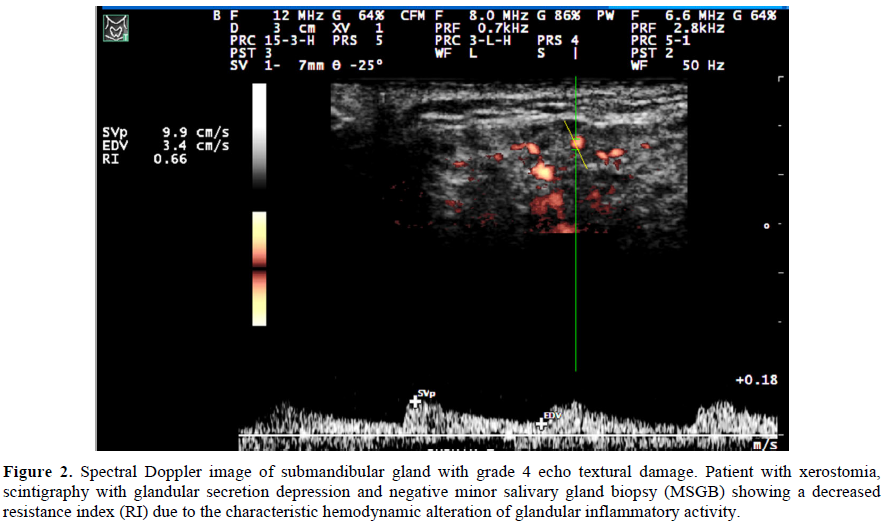

The spectral Doppler (SD), in addition to the gray scale (GS), is used to assess glandular vascularization [12,13]. The inflammatory process, by increasing glandular perfusion, generates hypervascularization and stimulates angiogenesis, resulting in hemodynamic changes measured by the variation in the resistance index (RI) [10].

Results: A total of 17 patients diagnosed with PSS, Caucasian, female, who suffered from xerophthalmia and xerostomia. Out of these, 15 (88.23%) had positive anti-Ro/SSA and 11 (64.70%) had positive anti-La/SSB. SGUS was used with 16 patients (94.11%) with grades ≥2, suggesting parenchyma heterogeneity characteristic of pSS. The average RI value found in our sample was 0.57 ± 0.10. Spearman's correlations between ultrasound (US) and laboratory variables showed statistical significance between SGUS with ESR (r=0.771 and p<0.00) and anti-La/SSB (r=0.499 and p=0.04). The RI showed statistically significant correlations with the C-RP (r=-0.647 and p=0.01) and anti-La/SSB (r=-0.647 and p=0.01).